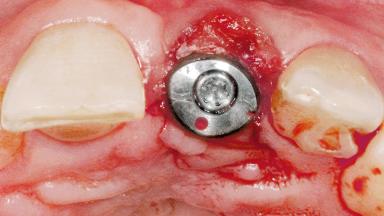

Late Flapless Placement of an Implant in a Maxillary Left Central Incisor Site

Type of Implants One-Piece

Attachment One-Piece

Bone Augmentation Horizontal|Staged

Augmentation Materials Xenogenous|Membrane

Soft Tissue Grafting Simultaneous

Bone Volume Deficient horizontally, requiring prior grafting